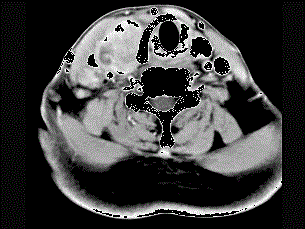

问题 女性,54岁,右侧颈部肿大近1年,近来病人有声嘶、吞咽困难,CT扫描如图,请选择正确的描述和答案 ( )

选项 A、考虑甲状腺癌 B、右侧颈内静脉瘤栓形成 C、增强扫描示甲状腺呈不规则强化团块影,其内有低密度区,病灶境界不清 D、右侧颈内静脉增粗,其内可见不规则充盈缺损区 E、右侧甲状腺肿大,密度减低

答案 ABCDE